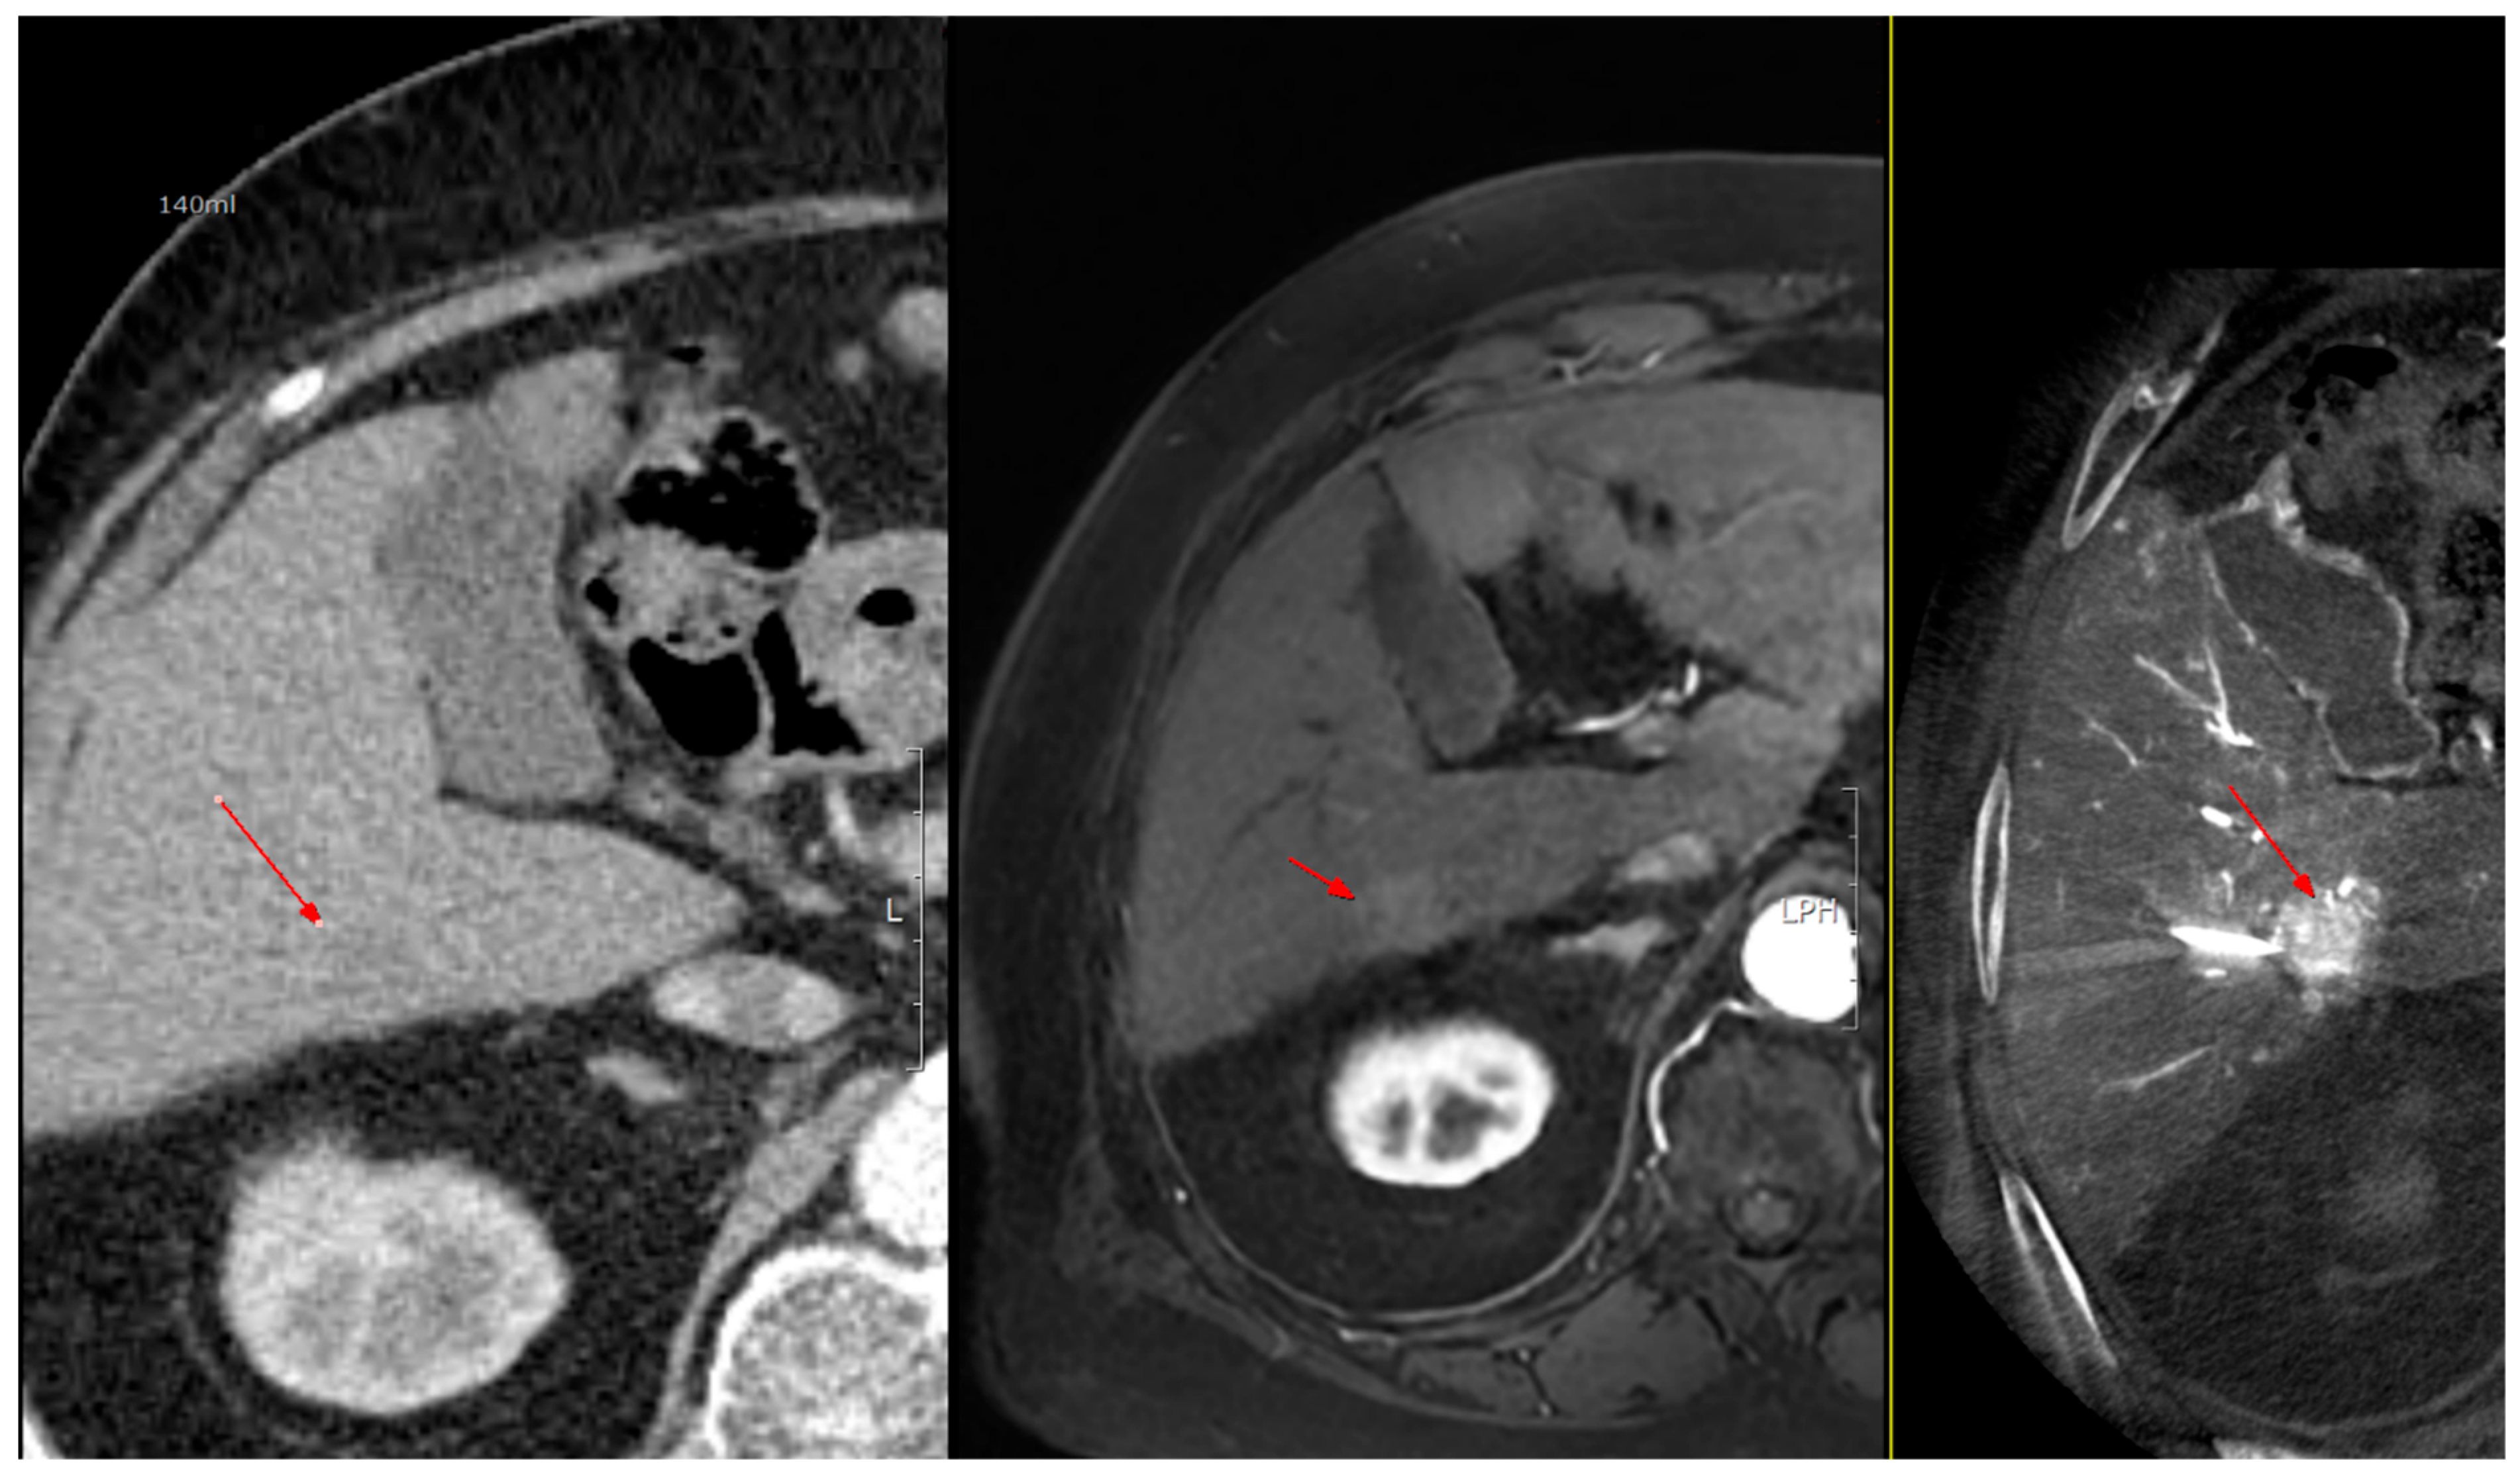

As shown in Figure 1, angio-CBCT allows for higher visibility of the target mass, as reflected in the ΔHU values. This can be visually confirmed in several cases. Representative cases in Figure 2 and Figure 3 demonstrate how the target mass is much more conspicuous to the operator on angio-CBCT compared to pre-procedural CT. In Figure 4, a mass, which was nearly invisible on pre-procedural CT, was identified through angio-CBCT, aiding the targeting process. Figure 5 shows a case where a mass with discordance between USG and CEUS was confirmed using angio-CBCT, leading to needle repositioning and achieving complete ablation. Finally, Figure 6 illustrates a case where a residual tumor was identified on angio-CBCT and re-ablation resulted in complete ablation.

Figure 4. Images from another patient with hepatocellular carcinoma undergoing angio CBCT-guided RFA. All red arrows indicate the HCC mass. (Left): pre-procedural CT (portal phase). (Middle): pre-procedural MRI (arterial phase). (Right): intraprocedural angio CBCT. (Intra lesion − Intra background = 432.7 HU).

Diagnostics 15 02898 g004